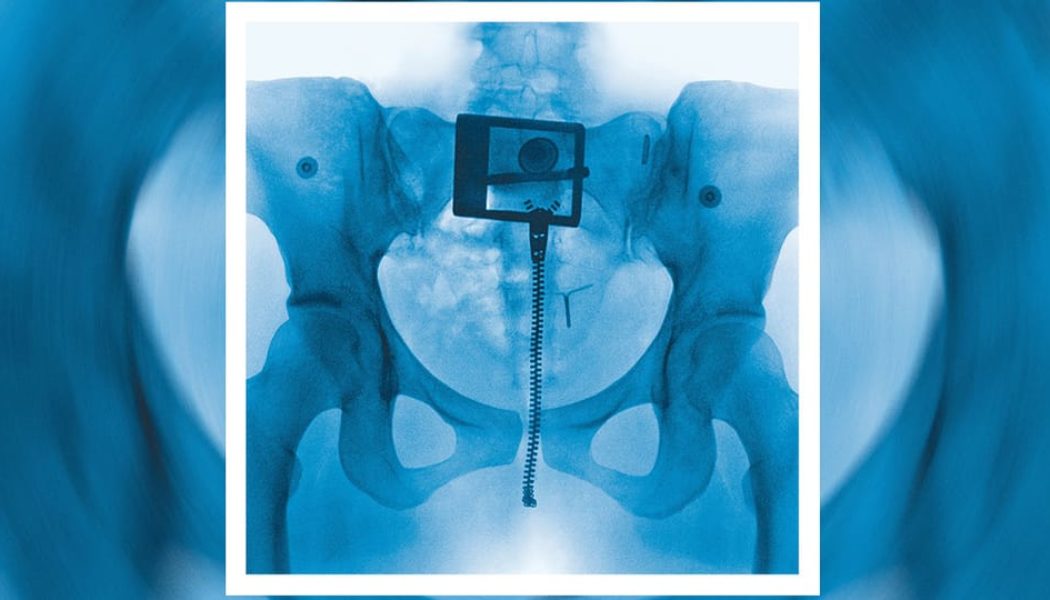

Lorde took to Instagram to share the official album artwork, which pictures a pelvic X-ray with a zipper, an IUD, and a belt buckle. In an email to fans, Lorde expounded on the inspiration behind the forthcoming record’s sound and visuals:

THE COLOUR OF THE ALBUM IS CLEAR. LIKE BATHWATER, WINDOWS, ICE, SPIT. FULL TRANSPARENCY. THE LANGUAGE IS PLAIN AND UNSENTIMENTAL. THE SOUNDS ARE THE SAME WHEREVER POSSIBLE. I WAS TRYING TO SEE MYSELF, ALL THE WAY THROUGH. I WAS TRYING TO MAKE A DOCUMENT THAT REFLECTED MY FEMININITY: RAW, PRIMAL, INNOCENT, ELEGANT, OPENHEARTED, SPIRITUAL, MASC.

I’M PROUD AND SCARED OF THIS ALBUM. THERE’S NOWHERE TO HIDE. I BELIEVE THAT PUTTING THE DEEPEST PARTS OF OURSELVES TO MUSIC IS WHAT SETS US FREE.